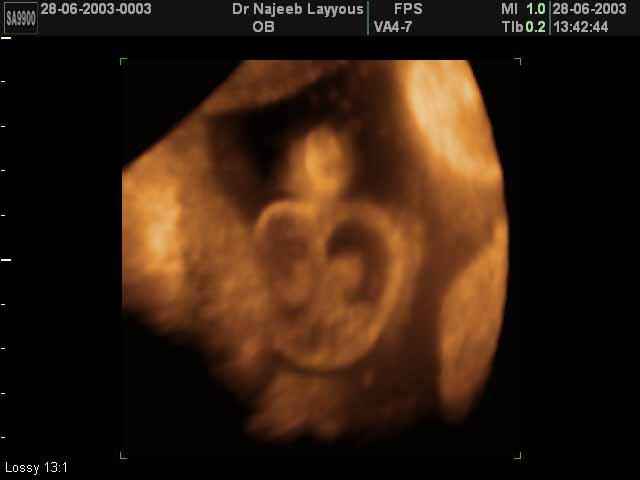

- لقطات فيديو للجنين بجهاز الموجات فوق صوتية رباعي الأبعاد

- صور لوجه الجنين في داخل الرحم

- صور لتصرفات الجنين داخل الرحم